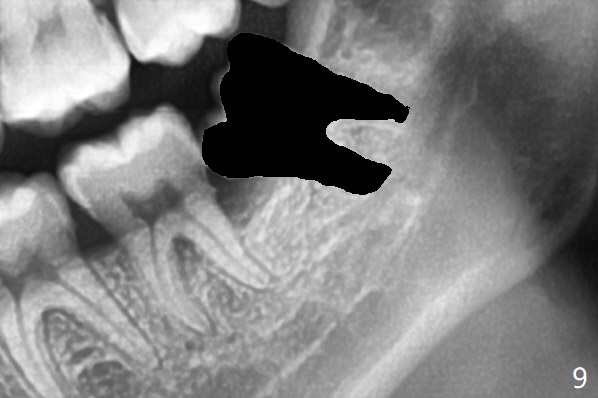

When the tooth #17 is extracted (Fig.9; 23 years old), collagen plug is inserted into the root portion of the sockets (Fig.10: 1 (white outline)), Vanilla graft is placed against the distal surface of #18 (2 (red outline)) and Osteogen plug (3 (green outline)) is placed coronally (3 steps). There is no bony defect associated with the distal surface of the tooth #18 immediate postop (Fig.11 (red dashed line: bone graft)). The wound heals in 2 weeks.